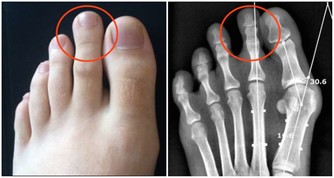

2.半月板損傷

半月板是一種彈性軟骨,位於股骨遠端與脛骨平台之間起緩衝作用,防止關節面軟骨受衝擊造成的損傷。半月板損傷主要由於外界暴力引起,也可以由自身退變引起。主要表現為屈伸活動時發生在關節內的彈響或突然“卡住”,多是因為破裂的半月板與脛骨、股骨發生異常的摩擦或嵌頓而產生。